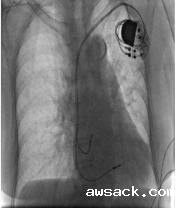

人工心脏起搏器植入术 ICD(植入式除颤复律仪) CRT(心脏再同步治疗)

人工心脏起搏器植入术:用特定频率的脉冲电流,经过导线和电极刺激心脏,代替心脏的起搏点带动心脏搏动的治疗方法,主要治疗重症慢性心律失常。